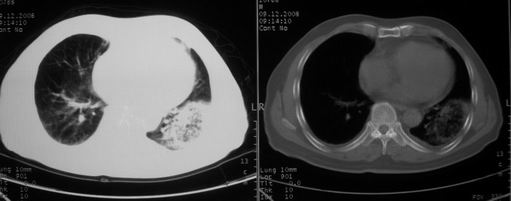

抗炎治疗一周热退,提示为炎症,现片示病灶范围增大,边缘清楚,建议继续治疗,不除外肺脓肿

炎症性病变;左侧胸腔积液。

ct左肺下叶大片状高密度影,病变密度不均,界限不清,左侧胸腔积液,治疗后复查临床症状好转而影像学表现病变有发展,还是首先考虑感染性病变,复查时间短附合感染性病变的病理改变。